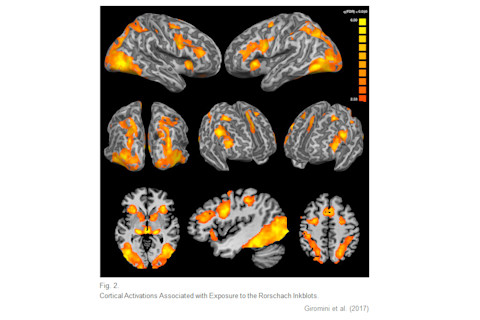

Unfortunately, the correlation between fractal dimension and number of percepts had a sample size of just five, because only half of Rorschach's ten blots were included in the analysis (as the others involve colors). Meanwhile, Italian researchers Luciano Giromini and colleagues conducted an fMRI study in which 26 healthy volunteers were shown the full set of blots and asked to "look at each inkblot and think of what it might be, trying to see only one thing per each inkblot design" Seeing the blots was associated with widespread increases in brain activity:

The authors go on to discuss what these patterns of activity mean. For example:

The Rorschach task strongly activated the anterior section of the thalamus, a large portion of the pulvinar, and part of the mammillary bodies. These areas are part of the limbic system and are thought to contribute to the perception and processing of emotions, especially in relationship to memory... From the point of view of the Rorschach assessment, thus, this finding is particularly intriguing. Essentially, it reveals that looking at the Rorschach inkblots while thinking of what they might be activates areas of the brain that are implicated in the perception and processing of emotions and emotional memories... As such, our study indirectly provides support to the idea that the Rorschach may be used to investigate the respondent's ability and willingness to focus on, talk about, and/or deal with emotionally loaded stimuli, contents and/or memories.

To be honest, this kind of functional interpretation of fMRI images has much in common with interpreting a Rorschach blot. Perhaps we're dealing with a case of Rorschach blobs? Yet there's a bigger problem here, which is that the brain activations probably weren't specific to seeing Rorschach images, but instead, just reflect the neural response to any complex visual stimulus. This is because Giromini et al.'s baseline condition was a fixation cross, i.e. seeing a + on the screen. The cross stimulus is less complex, and smaller, than a Rorschach image (and less colorful in the case of the 5 colored blots.) So we can't interpret the fMRI blobs as being Rorschach-specific. The authors do acknowledge this limitation, but they don't seem to recognize that it's a fatal one.